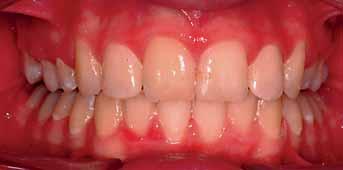

Treatment objectives were achieved and the patient was satisfied with the treatment outcome. The overbite and overjet were reduced, Class I incisors, canines and full unit class II molars were obtained. Overall treatment time was twenty four months

Upon the completion of the space closure stage, some finishing details were carried out. Although some more correction was still needed to be done e.g. the marginal ridge of the upper left second premolar and the palatal root torque in the upper incisors (Figure 9). Furthermore, taking an OPG towards the end of treatment to assess the roots angulation, nonetheless, the patient preferred to have the appliances removed and he was satisfied with the outcome.